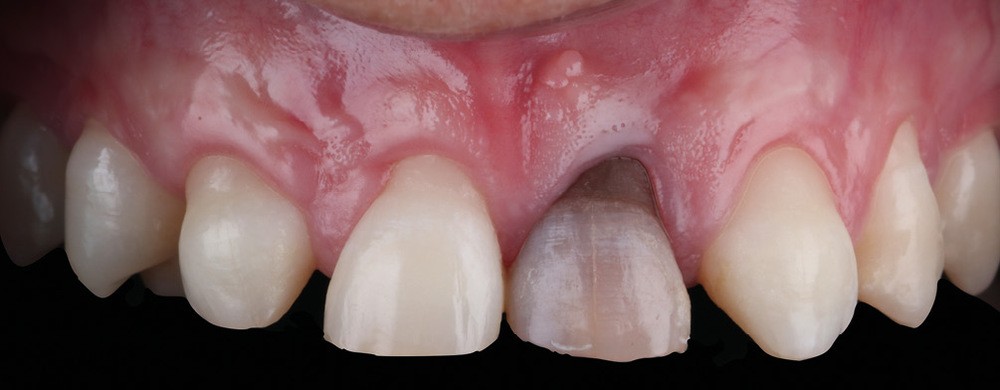

Acte 5 : choix des chapes pour la future stratification (fig. 7 et 8)

Nous faisons face à une double difficulté : il s’agit d’obtenir la similitude entre les deux centrales (dents miroir), mais aussi entre les chapes zircone à sceller sur les quatre couronnes antérieures et les chapes disilicate de lithium à coller en secteur postérieur.

Les chapes choisies doivent être assez translucides pour laisser passer la lumière mais suffisamment opaques pour masquer les défauts des substrats et les différences de préparations dentaires sous-jacentes.

- Pour l’incisive centrale 21 présentant une forte dyschromie (la difficulté majeure du rendu colorimétrique globale finale), deux pièces sont réalisées. Une première chape en zircone LT (light translucidity) a pour but d’harmoniser les substrats, tout en masquant la dyschromie sans que cela ne soit trop opaque et ainsi pouvoir finir sur une limite cervicale, en zircone polie qui puisse s’intégrer de façon esthétique à la zone cervico-gingivale et créer une meilleure attache épithéliale à ce niveau. Pour la chape secondaire 21, notre choix se porte sur un matériau zircone MT1 (middle translucidity), une zircone claire mais néanmoins translucide, apportant, contrairement à un matériau opaque, une diffusion de la lumière et, de ce fait, un rendu naturel.

- Pour les chapes des dents 11, 12, 22 le même matériau (zircon middle translucidity) est choisi, complétant ainsi l’accord de couleur avec la chape 21.

- Pour les armatures facettes 13, 23, 14 et 24, nous optons pour du disilicate (lt bleach 3), ce matériau étant celui qui se rapproche le plus de l’aspect des armatures zircone MT en termes de teinte, de translucidité et de luminosité. Ceci dans un souci d’harmonie des armatures et du résultat final.